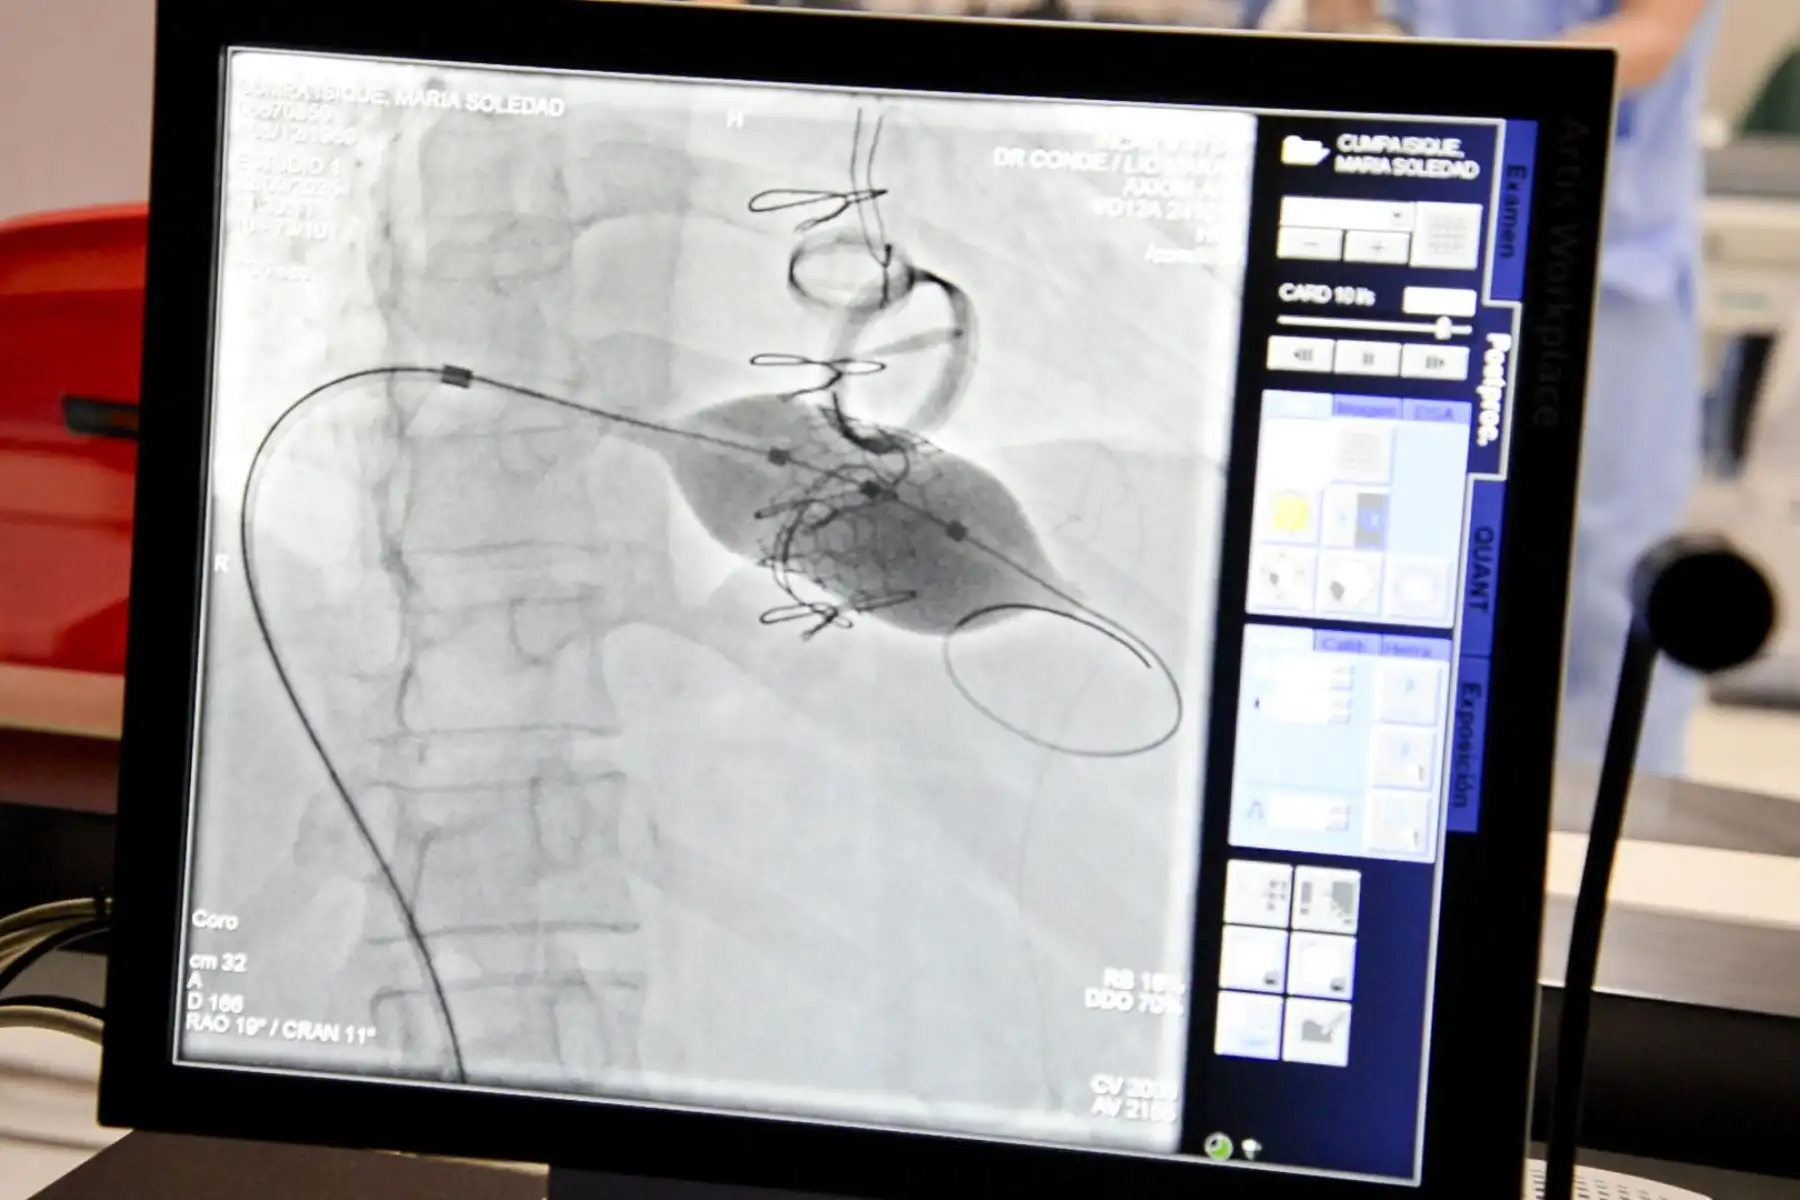

25/10/2025 Durante muchos años, María Cumpa convivió con la fragilidad de un corazón que había sido operado tres veces. Le reemplazaron las válvulas aórticas, mitral y tricuspídea. Cada operación fue una batalla ganada, pero también una nueva marca en su cuerpo y en su ánimo. Con el paso del tiempo, una de esas válvulas volvió a fallar. Su salud se deterioraba y una cuarta cirugía a sus 55 años era un riesgo demasiado alto.